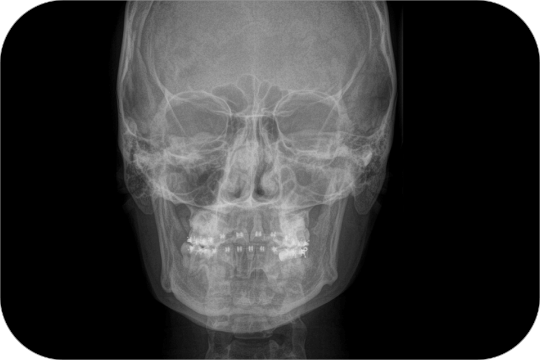

Antero Posterior